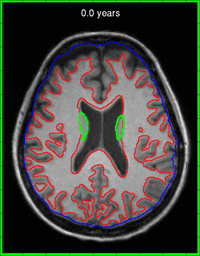

Fig. 5. Animation of model estimated with image and shape data. A green border around the image represents interpolation within the observation interval (3 years). A red border represents extrapolation out to 10 years from baseline.

The trajectory of caudate volume extracted after regression is shown in Fig. 5. The model estimated from images alone fails to capture the volume loss observed in both caudates, and rather, shows an increase in right caudate volume. By incorporating caudate shape data in model estimation, we are able to capture the shrinking of the caudates. The corresponding expansion of the ventricles is also captured, shown in Fig 4, due to the inclusion of imaging data. By incorporating shape and image information jointly, we are able to model both the expansion of the ventricles and the degeneration of the caudates. Accurate models of change are essential when extrapolating beyond the observation time interval, which can provide insight into disease progression.

We investigate the application of joint image and shape regression to Huntington’s disease (HD) where accurate 4D models are needed to measure the effectiveness of therapies or drug treatments. In HD, degeneration of the caudate has been shown to be significant. Here we explore T1W image data from a single patient diagnosed with HD scanned at 58, 59, and 60 years of age. Sub-cortical structures are segmented, manually verified, and cleaned. Models are estimated using only T1W images as well as T1W images plus caudate surfaces.